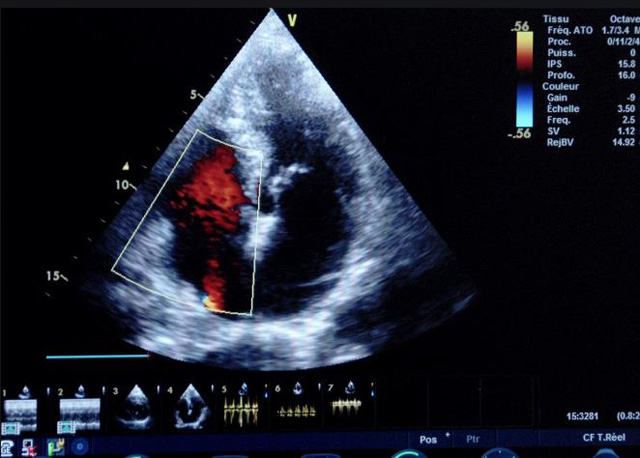

二、彩色室壁運(yùn)動分析

(一)基本原理彩色室璧運(yùn)動分析,從整體散射數(shù)據(jù)中識別心內(nèi)膜邊界,并與前一幀彩色不同,心臟收縮或舒張期開始到結(jié)束時心內(nèi)膜的全部過程。每一次順序顯示結(jié)束后,原來的彩色自動消失,以便進(jìn)入下一個顯示過程。其結(jié)果是獲得對應(yīng)于每一個心動周期的彩色顯示,描繪特定周期內(nèi)室壁運(yùn)動的時間運(yùn)動軌跡。

(二)操作步驟根據(jù)背向散射數(shù)據(jù)中將心內(nèi)膜運(yùn)動的位移過程分類為組織或血液的原理,邊緣檢測跟蹤心內(nèi)膜和血液的界面。橙色表示收縮期的開始,收縮期不同時相逐幀顯示色彩均疊加在收縮末期最后一幀圖像中。檢查時,可按以下步驟進(jìn)行:

①顯示較為理想的二維圖像,常用切面有心尖四腔心、二腔心、左心室長軸和左心室乳頭肌水平短軸切面。

③啟動CK系統(tǒng),啟動后劃定感興趣區(qū)域。同時記錄的心動圖R波頂點為舒張末期,T波終點為收縮末期,顯示RT間期的CK彩階圖,連續(xù)記錄3~ 5個心動周期。

(三)檢測節(jié)段性室壁運(yùn)動異常,研究冠心病患者左心室功能和分析局部室壁運(yùn)動過程中。測量每一節(jié)段室壁的運(yùn)動量,運(yùn)動正常的節(jié)段彩帶色彩均勻?qū)哟喂庹?。運(yùn)動減弱的節(jié)段,厚度薄層次不全。心內(nèi)膜位移幅度和速度均減低。心內(nèi)膜位移幅度和速度甚低或難以測得。正常的多層彩帶消失,呈現(xiàn)紅色色帶,心內(nèi)膜位移呈負(fù)向,幅度和速度亦減低。急性心肌梗死的患者中可用于識別存活心肌抑或壞死心肌。多巴酚丁胺負(fù)荷試驗存活心肌的心內(nèi)膜位移幅度增高,停藥后即消失,而壞死心肌則無上述表現(xiàn)。實時檢查冠心病的節(jié)段性室壁運(yùn)動異常,有時候通過發(fā)現(xiàn)局部心肌運(yùn)動的時相異常,對于心臟傳導(dǎo)障礙的診斷也可能有幫助。